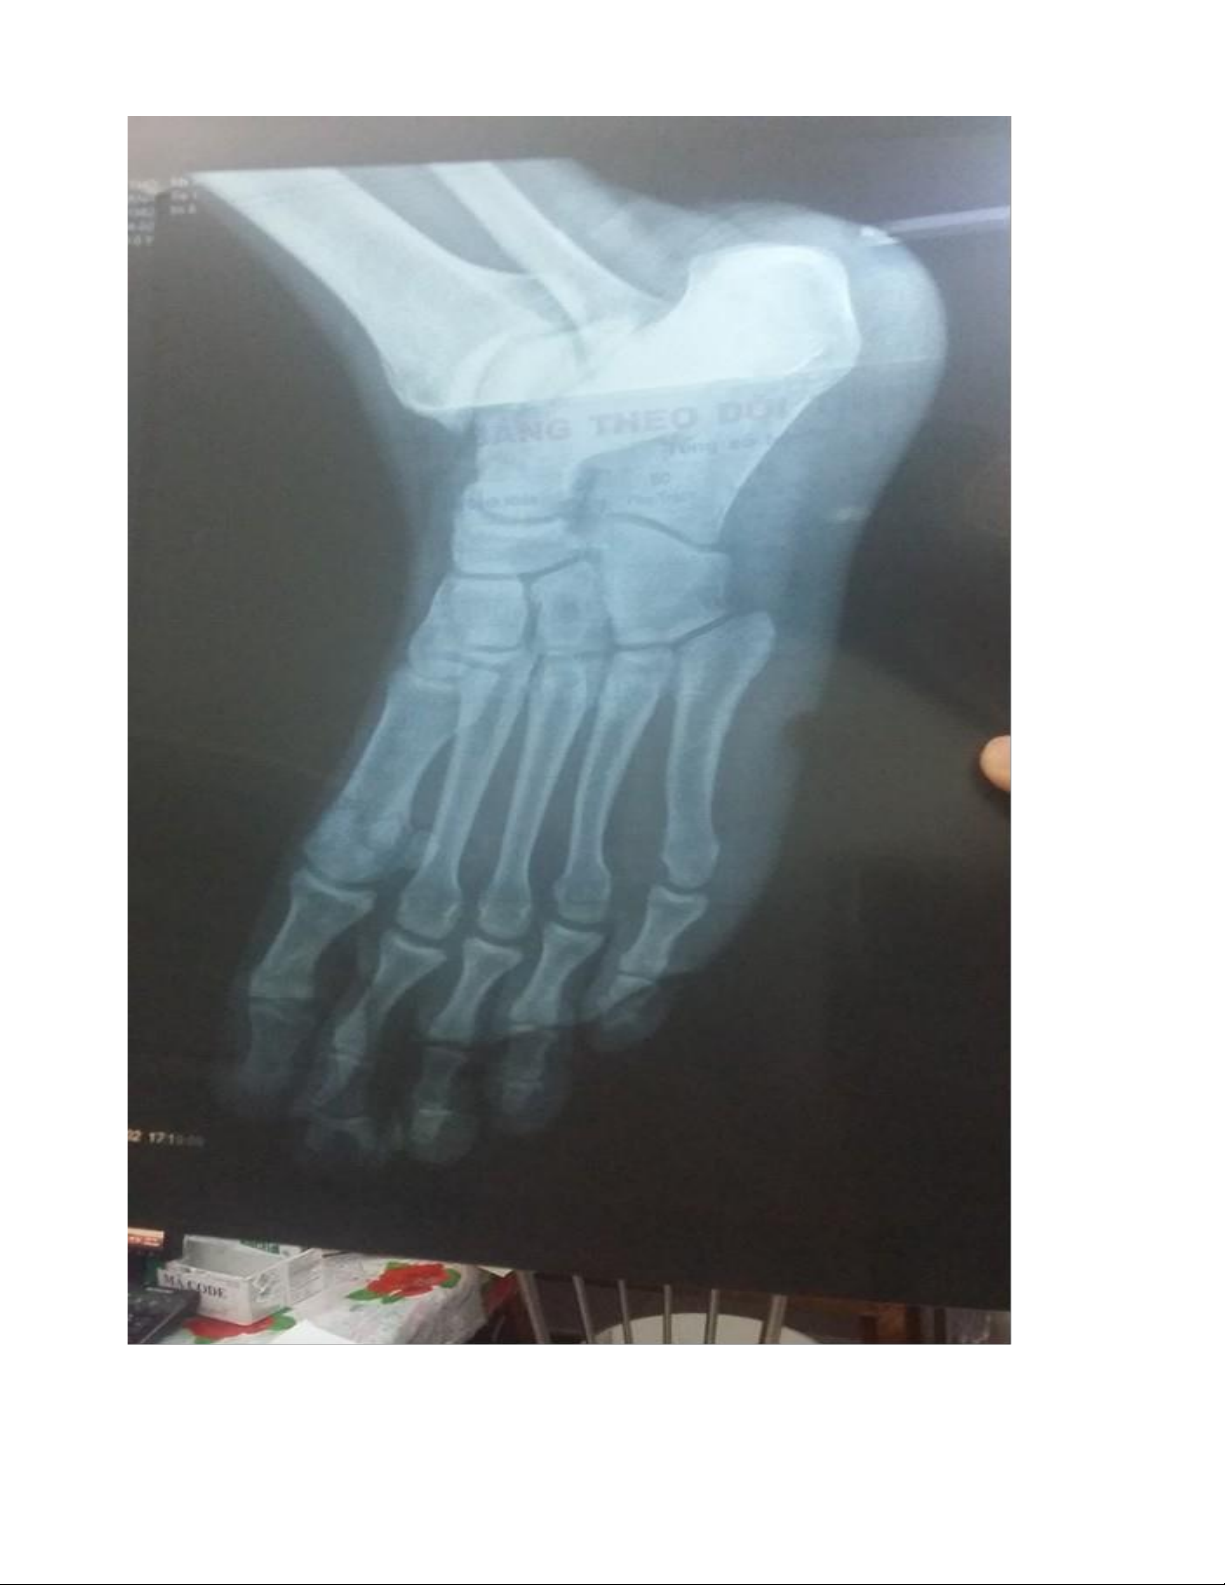

Cận lâm sàng: X quang cẳng chân (Thẳng-nghiêng), X quang ngực thẳng,

Công thức máu, Đường máu mao mạch, HbA1C, Urea, Creatinin, Glucose, Na+ K+ Cl-, ECG, PT, APTT Kết quả cận lâm sàng

- X quang: Chưa ghi nhận tổn thương xương.